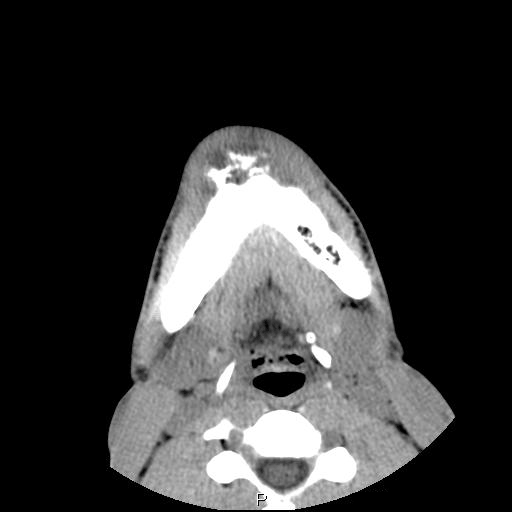

Clinical information The patient was a 23 year-old man who went to see the dentist because of dull pain, swelling of the chin,  and loosened lower front teeth. He was referred to this hospital after initial examination. A CT scan was performed and and a biopsy was taken. Representative images are presented here. Panel D is a sagittal reconstruction from axial CT scans. A resection was subsequently performed.

CT scan: On the CT scan images (Panel A, B, C, and D), two lesions are present.  There is a lesion at the mental protuberance that appears to have penetrated the cortex and invaded into the soft tissue. The patchy hyperdensity strongly suggests that this lesion has mineralize elements ( in Panel B). The border of the lesions in the mandible is poorly defined. The penetration of the bone and extension into the soft tissue is best appreciated in the sagittal reconstruction in (Panel D). These features are highly suggestive of a malignant neoplasm that originates from the bone with extension into surrounding soft tissue. The hyperdensity of the mass suggests bone formation and the radiologic features are suggestive of an osteosarcoma. In the right body of the mandible, there is a diffusely expansile lesion  with some hazy hyerdensity (Ú in Panel B). The cortical bone overlying this lesion is intact. This lesion may represent extension of the osteosarcoma into the body. However, it may also represent a co-existing fibrous dysplasia.